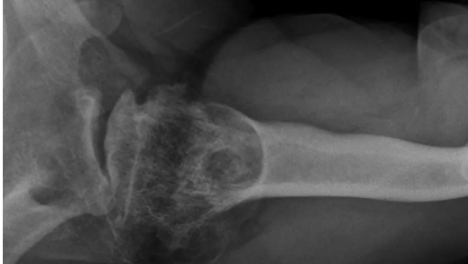

Cuando se produjo la emergencia, dos buzos descendieron para intentar rescatarla. Ambos debieron recibir posteriormente atención médica por accidentes de descompresión tras regresar a la superficie y esa misma noche fueron ingresados a una cámara hiperbárica.